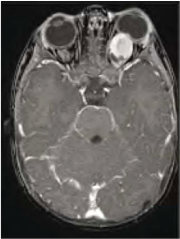

| 10:13, 5 באוגוסט 2014 | Neurofibromatosis 8.png (קובץ) |  |

174 קילו־בייטים | Motyk | 1 | |

| 10:11, 5 באוגוסט 2014 | Neurofibromatosis 7B.png (קובץ) |  |

80 קילו־בייטים | Motyk | 1 | |

| 10:11, 5 באוגוסט 2014 | Neurofibromatosis 7A.png (קובץ) |  |

102 קילו־בייטים | Motyk | 1 | |

| 10:06, 5 באוגוסט 2014 | Neurofibromatosis 6.png (קובץ) |  |

221 קילו־בייטים | Motyk | 1 | |

| 10:01, 5 באוגוסט 2014 | Neurofibromatosis B.png (קובץ) |  |

232 קילו־בייטים | Motyk | 1 | |

| 10:00, 5 באוגוסט 2014 | Neurofibromatosis 5.png (קובץ) |  |

304 קילו־בייטים | Motyk | 1 | |

| 06:54, 5 באוגוסט 2014 | Neurofibromatosis 4.png (קובץ) |  |

133 קילו־בייטים | Motyk | 1 | |

| 06:53, 5 באוגוסט 2014 | Neurofibromatosis 3.png (קובץ) |  |

131 קילו־בייטים | Motyk | 1 | |

| 06:51, 5 באוגוסט 2014 | Neurofibromatosis 2.png (קובץ) |  |

215 קילו־בייטים | Motyk | 1 | |

| 06:38, 5 באוגוסט 2014 | Neurofibromatosis 1.png (קובץ) |  |

214 קילו־בייטים | Motyk | 1 | |